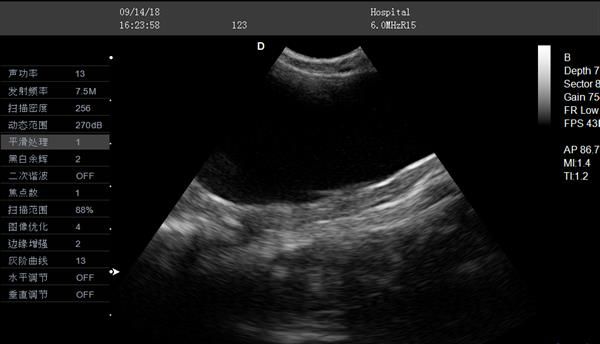

近日有宠物医院咨询笔记本式的b超机的价格是多少,其实笔记本式的b超机的价格受很多因素的影响,比如生产厂家、探头等,因此笔记本式的b超机的价格并非是固定的。而大为医疗的L3-VET彩色多普勒动物超声诊断仪因图像清晰、便于携带,电池续航能力强,性价比较高,价格适中,深受宠物医院的青睐。

大为L3-VET便携式兽用彩超机,不仅可以满足综合性兽医和宠物医院的各种检查的需求,为兽医提供优质的图像和全方位的临床解决方案,而且能够满足兽医日常的临床诊断需要,同时也兼顾教学科研等多方面的应用。

L3-VET笔记本兽用B超机不仅适用于中小型动物孕检,还可以用来检测中小动物的肝、胆,脾、肾、膀胱、子宫等各组织器官及病变的诊断。也可以用来检测爬行类妊娠诊断,鱼类性别鉴定的诊断。

另外,L3-VET笔记本兽用B超机还可以用于牛、羊、马、猪、骆驼等大型动物孕期检查和背膘厚度测定,臀部脂肪和肌肉的测定。